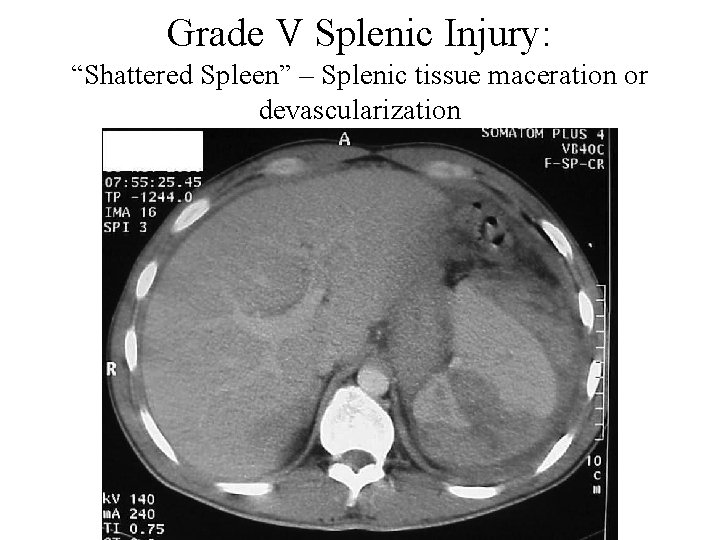

Grade V Splenic Injury: “Shattered Spleen” – Splenic tissue maceration or devascularization